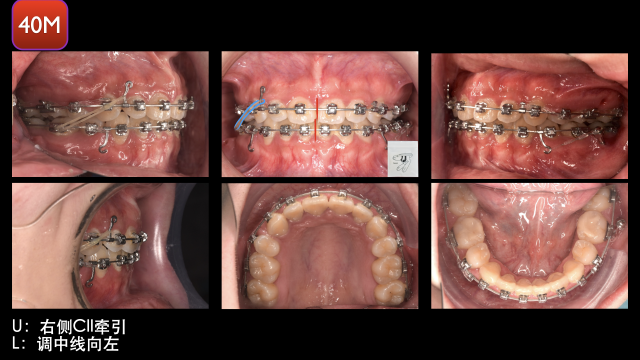

术中治疗